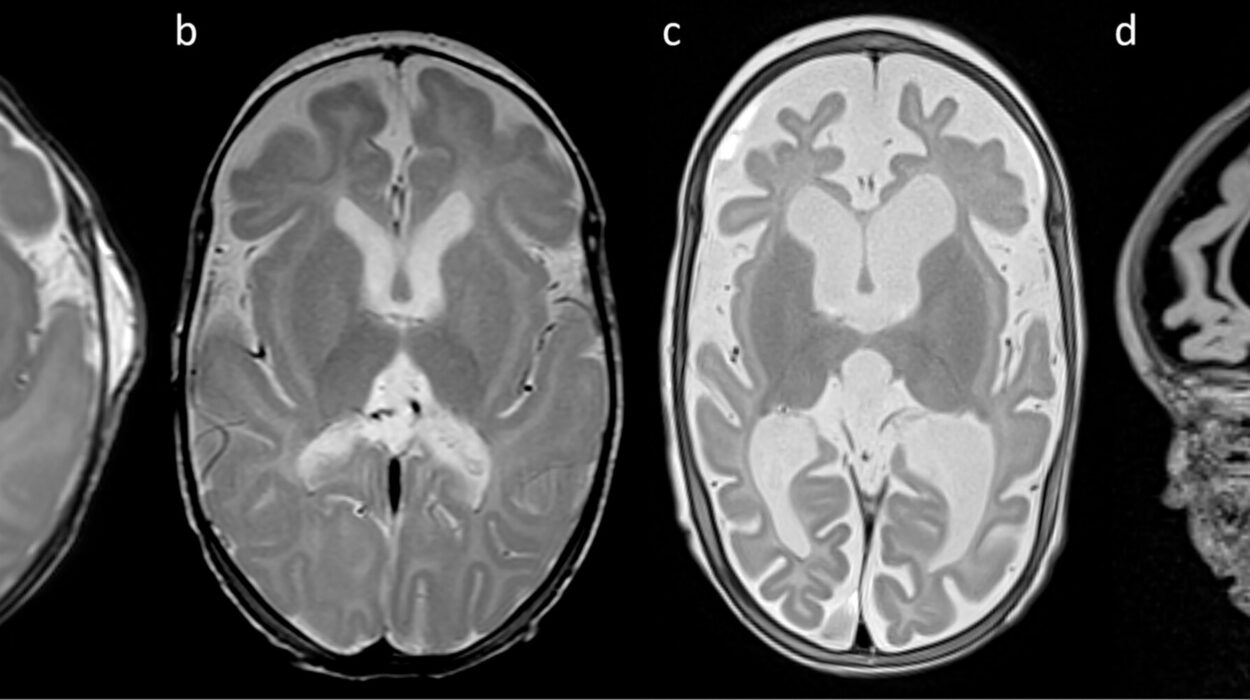

The human brain regulates fear and anxiety through intricate networks involving neurotransmitters such as serotonin, dopamine, norepinephrine, and gamma-aminobutyric acid (GABA). Imbalances in these chemical messengers can disrupt communication between brain regions like the amygdala (responsible for fear responses) and the prefrontal cortex (responsible for rational thought and regulation).

Overactivity in the amygdala, for example, can heighten fear responses, while underactivity in the prefrontal cortex reduces the brain’s ability to calm those responses. This imbalance creates a fertile ground for chronic anxiety.